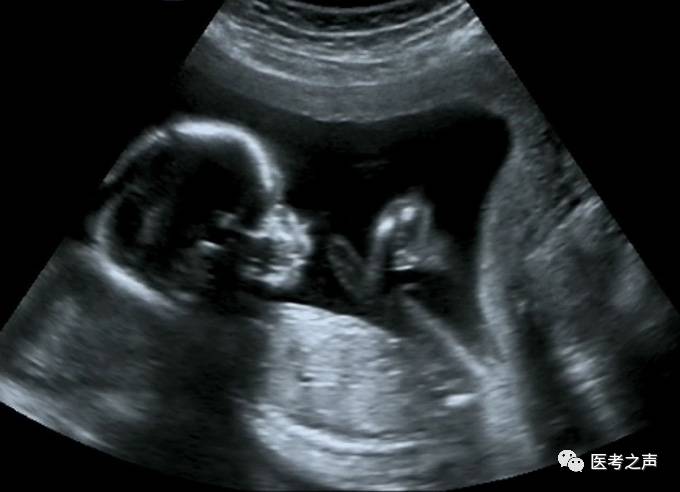

B超

像挑西瓜前敲一敲

B超检查是利用超声波产生回声的原理来检查的。超声能向一定方向上传播,而且可以穿透物体,如果碰到障碍,就会产生回声,人们通过仪器将这种回声收集并显示在屏幕上,可以用来了解物体的内部结构,辅助诊断。就像挑西瓜一样,边敲边看显示病灶情况。B超是两个维度的超声信息,构成平面图形,反映人体结构。

此外,孕期做B超检查的目的是判断胎儿生长是否符合孕周,判断胎儿有否畸形,了解胎儿在子宫内是否安全。